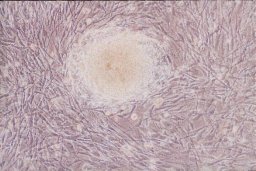

First off, there is no ban on stem cell, embryonic stem cell, adult stem cell, cord blood stem cell, or any kind of of stem cell research. At all. There is no ban on harvesting them from embryos (no matter the source, in vitro clinics, etc), adults, or crack heads off the street. You can do research on any aspect of stem cells harvested from whatever you want. Then entire debate (and the recent bill) is over whether or not the federal government should fund stem cell research.

Secondly, there is no ban, much to my chagrin, on federal funded research into stem cells. The Bush administration decided that there was a cut off date in 2001 and that any research done on lines of stem cells harvested before that point were fully usable for federally funded projects. If you wonder why you can't receive federal funding for research using stem cells harvested after that point, well, Bush's target demographic are right wing Christians, and any debate about this eventually leads to the slippery slope of abortion. Not an argument I want to delve into here. Just suffice to say that you can get (grr) federal funding for stem cell research. Not only is there not a ban, you can get the government to foot the friggin' bill.

With all that said, I think stem cell research is possibly one of the most promising things to come out of medicine ever. So why do I sound vehemently opposed to any federal funding of stem cell research? I quote Samuel Broder, former researcher at the National Institutes of Health and former director at the National Cancer Institute:

"If it were up to the NIH to cure Polio through a centrally directed program you'd have the best iron lung in the world but not a polio vaccine."

In addition, me being a fiscally conservative fellow, despises the idea of tax money going to fund research. Oh, you think without that money we'll never get anywhere? Oh wait, human Embryonic Stem Cells were isolated and cultured for the first time in 1998 using privately funded research, after Clinton(!!!) signed off on the Dickey Amendment, banning federal funding for any research that involves either creating an embryo, or destroying an embryo in the course of the research. Damn, how'd they pull that off?